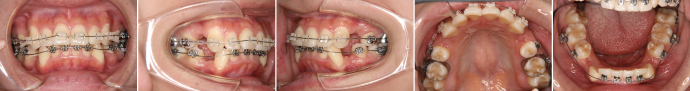

| 主訴 | 上の前歯が出ている、下の前歯がデコボコ |

| 年齢・性別 | 26歳 / 女性 |

| 治療方針 | 顎関節に少し問題があるAngleⅠ級上下顎前突。患者の希望もあり、できるだけ前歯を後退して口元の突出感の改善を行う。 |

| 抜歯部位 | 小臼歯4本抜歯 |

| 使用装置 | ホールディングアーチ、マルチブラケット装置 |

| 治療期間 | 26か月 |

| リテーナー | 上顎インビジブル、下顎スプリングリテーナー |

| 費用 | 825,000円(税別) |